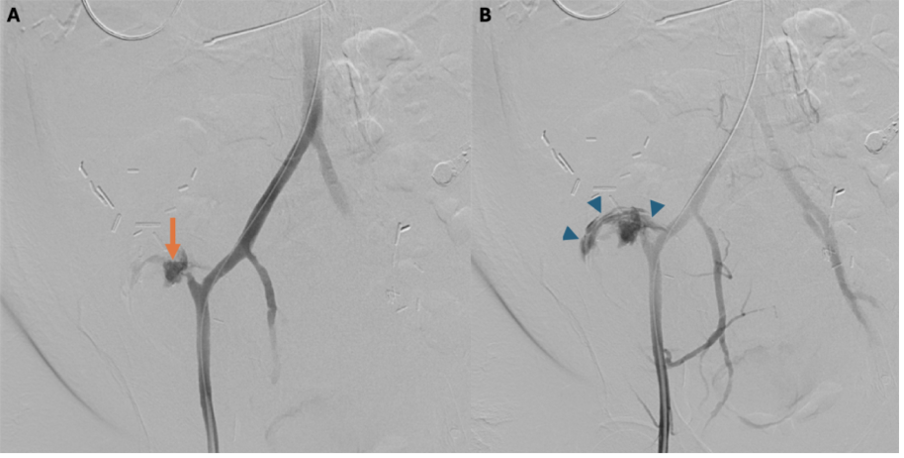

Treatment and Management. After recognizing the critical nature of the bleed soon after the CT scan, there was immediate face-to-face coordination with anesthesia and the critical care team. The patient initially required resuscitation in the CT suite; however, with timely cooperation, she was brought to the interventional radiology suite within 30 minutes of completion of the CT scan. Under general anesthesia, right common femoral artery access was obtained via ultrasound guidance, and angiography confirmed rapid active bleeding from the arterial conduit of the pancreas transplant (Figure 3).

Figure 3. (A) Angiogram of the arterial conduit demonstrates the pseudoaneurysm (arrow). (B) A slightly delayed angiographic frame shows contrast extravasation (arrowheads) outlining the bowel lumen and confirming the presence of an arterio-enteric fistula.